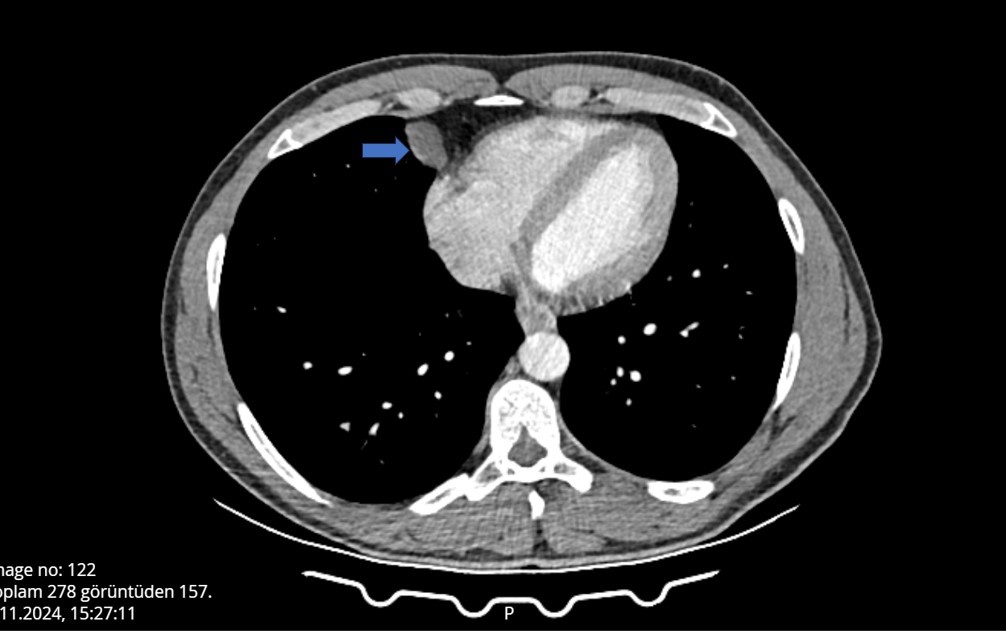

Burada tomografisi çekilen Can'ın, akciğer ile kalbinin arasında bir kist olabileceği belirtildi.

Can, çevresindekilerin tavsiyesi üzerine detaylı araştırma ve inceleme için, Antalya Eğitim ve Araştırma Hastanesine başvurdu. Gerekli tetkikleri yapılan Ömer Can'ın, belirtilen bölgesinde yaklaşık 2 santimlik bir kist olduğu tespit edildi ve hemen ameliyata alındı. Göğüs Cerrahi bölümünde Video Yardımlı Torakoskopik Cerrahi (VATS) yöntemiyle gerçekleşen ameliyat yaklaşık 10 dakika sürdü. Hastanede ilk kez tüpsüz olarak gerçekleştirilen ameliyat sonrası Ömer Can sağlığına kavuştu, 1 gün sonrası ise taburcu edildi.

Antalya Eğitim ve Araştırma Hastanesi Göğüs Cerrahi Kliniği Eğitim Sorumlusu Doç. Dr. Muharrem Özkaya, hastanın çekilen tomografisinde, akciğerin altında, kalbin yanında perikardiyal kisti bulunduğunu ve VATS yöntemiyle iki delikten girerek kisti aldıklarını anlattı. Normalde bu tarz ameliyatlarda göğüs tüpü kullanıldığını aktaran Özkaya, “Hastanın en büyük sıkıntısı bu tüpten dolayı. Şiddetli ağrıları olur ve taburculuğu uzar. Biz göğüs tüpü takmadan ameliyattan çıktık, operasyon 10 dakika sürdü ve bugün taburcu etmeyi planlıyoruz” dedi.